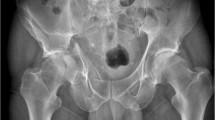

Since its inception, 3D-printed PSI has not had widespread application within paediatric orthopedic surgery. This trend seems to be changing though; based on the limited available evidence, PSI appears to be effective for application in deformity correction about the femur and pelvis. From our review, it was found to be simple to use, facilitated clear pre-operative planning and effective intraoperative implementation of that plan (see Additional file 2: image 1) while removing the need for continuous intraoperative fluoroscopic monitoring - this in particular leading to a further reduction in operative times and perhaps more importantly lessening the potential harmful effects of unnecessary radiation exposure to patient and operating team.